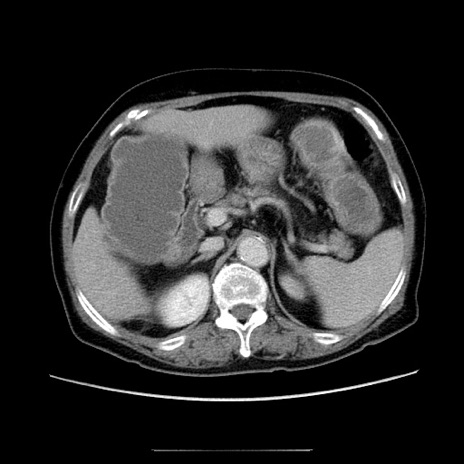

症例5(横断像)

【症例】70歳代女性

【主訴】お腹が張る

【現病歴】1週間くらい前から腹部膨満の自覚あり。昨日夜から増悪したため、本日救急外来受診。

【身体所見】意識清明、BT 36.5℃、BP 165/106mmHg、HR 80bpm、SpO2 98%、腹部:膨満、軟、自発痛・圧痛なし、触診にて不快感あり、腸蠕動音:減弱

【データ】WBC 12600、CRP 1.04